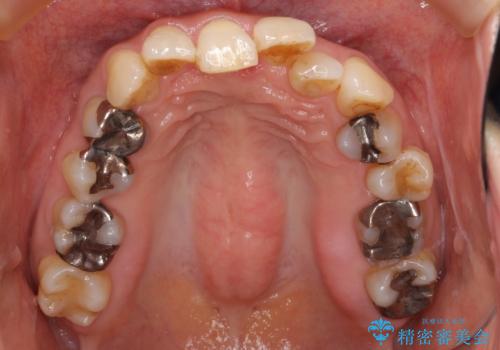

かみ合わせが深く、上の歯が咬みこんで下の歯にワイヤーがつけられない状態で、ワイヤー矯正はかなり難しい状態でした。

反対咬合や、すれ違い咬合もあり、大変難しいケースでしたが治療することができました。

かみ合わせが深い方はもともとかみしめが強く、マウスピース矯正を長期にすると、奥歯が咬まなくなってくる症状が強くなります。

今回もそういった状態になったのを、装着時間や歯の移動を工夫する形で治療しました。